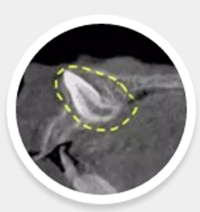

CBDT顯示:恒牙牙胚旋轉(zhuǎn)90度,牙根開始彎曲發(fā)育:

4.png

這種情況如果不給予干預(yù)會怎樣?

牙根發(fā)育過程中會由于周圍硬骨板的阻擋而導(dǎo)致牙根彎曲發(fā)育,最終會發(fā)展成上面淘淘牙齒所出現(xiàn)的情況。

慶幸的是欣欣這顆牙齒根尖口未完全閉合,呈喇叭口樣,我們可以用正畸的方式試著來牽引,改變牙冠的方向,讓牙根繼續(xù)按正常的位置發(fā)育!